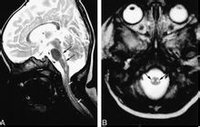

腦幹腦炎患者,女,35歲,湖南衡陽市郊農民。因行走無力,視物模糊5天,加重伴言語不清,嗜睡2天,於2005年11月24日急診入院。2005年11月20日上午,患者在廣州某鎮探親時家務勞動後,上樓時出現行走無力,下午自覺視物模糊,不伴發熱、惡寒、頭痛、頭暈、咳嗽、咽痛、噁心、嘔吐等症狀。11月21日上午患者步行到廣州市某鎮醫院按"上呼吸道感染"治療無效。11月22日下午患者出現行走無力加重,需人攙扶,並出現言語欠清晰、精神差,被家人於當晚送回湖南當地縣人民醫院診治。查體:嗜睡,反應遲鈍,言語欠清晰,口角向左歪,伸舌右偏,右上下肢肌力IV級,左上下肢肌力正常,病理反射(-)。頭顱CT平掃未見異常。按"腦梗塞"治療病情無好轉,故於11月24日下午轉至我院神經內科重症監護病房按重症腦梗塞診治。入院時查體:T36.7℃P86次/分R20次/分BP105/71mmHg嗜睡,言語欠清晰,右眼瞼稍下垂,右眼內收及左眼外展受限,右側鼻唇溝稍變淺,伸舌右偏,雙側咽反射減弱,心、肺、腹均未見異常,左上、下肢肌力IV級加,右上、下肢肌力III級加,四肢肌張力稍低,腱反射減退,指鼻及輪替試驗及感覺功能檢查無法配合。頸軟,克、布氏征(-),右巴氏征(+),左巴氏征(-)。實驗室檢查:血常規:WBC總數:10.4×109/L,分類正常;電解質、肝、腎功能、血脂、血糖及血氣分析均正常。11月25日上午患者出現昏睡,完全性失語,四肢肌力明顯減退,右上肢肌力0級,左上、下肢及右下肢肌力均II級。查頭顱MRI示:中腦與橋腦交界處見片狀稍長T1稍長T2信號,邊界欠清晰,中腦導水管及第四腦室未見明顯受壓;頭顱MRI增強:腦幹異常信號,未見明顯強化,考慮腦幹梗塞。11月26日患者陷入淺昏迷,腰穿查腦脊液壓力95mmH2O,外觀無色,清亮,潘氏實驗(+),總蛋白定量0.58g/L,白細胞數76×106/L,單個核細胞90%,多個核細胞10%,葡萄糖2.59mmol/L,氯化物117mmol/L,故診斷為腦幹腦炎,給予地塞米松10mg靜滴,每日一次,同時予抗病毒,抗感染等治療,12月2日患者意識轉清醒,但言語模糊不清,右上肢肌力II級,右下肢肌力0級,左上下肢肌力II-III級。14天后停地塞米松改為口服強的松30mg/天,逐漸減量,患者入院第20天因經濟困難出院,出院時查體:右眼內收及左眼外展受限,伸舌稍右偏,雙上肢肌力III-IV,雙下肢肌力III級,病理征陰性,複查腦脊液:壓力180mmH2O,無色,清亮,潘氏實驗(-),腦脊液蛋白定量0.23g/L,白細胞數16個106/L,單核細胞為主,葡萄糖3.4mmol/L,氯化物128mmol/L。2006年1月17日複診:患者仍行走不穩,需人攙扶。查:神清語利,計憶力、定向力、記算力正常,雙眼球運動正常,雙鼻唇溝對稱,伸舌稍右偏,四肢肌力肌張力正常,雙巴氏征陽性,深淺感覺檢查正常。雙側指鼻試驗稍差,Romberg征睜眼(+),閉眼(+)。腦電圖正常;視覺、腦幹聽覺誘發電位檢查:右眼VEP潛伏期延長,波幅在正常範圍內;左眼VEP潛伏期、波幅在正常範圍內;右耳BAEP波形分化不良,左耳BAEPⅠ、Ⅲ、Ⅴ波幅,潛伏期正常;四肢肌電圖檢查:左腓總神經運動傳導波幅降低。2006年3月15日隨訪,患者行走正常,完全康復。查體無異常。